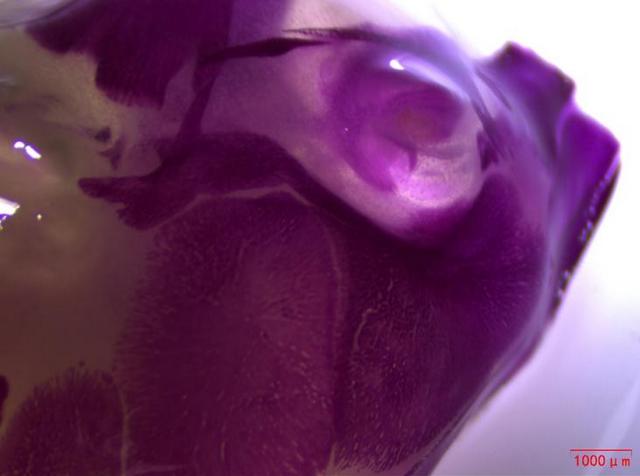

近日,湖南某生物企業(yè)引進(jìn)了Mshot明美生產(chǎn)的體視顯微鏡MZ101,用于觀察小動(dòng)物大體組織,如小鼠幼崽的脊柱和頭部。體視顯微鏡MZ101以成像清晰、超長(zhǎng)工作距離和大視野目鏡等顯著特點(diǎn),為生物企業(yè)的科研人員提供了良好的觀察體驗(yàn)。

在動(dòng)物實(shí)驗(yàn)研究領(lǐng)域,對(duì)小動(dòng)物大體組織的清晰觀察至關(guān)重要。明美體視顯微鏡MZ101憑借其高分辨率和優(yōu)異的光學(xué)性能,能夠捕捉到小鼠幼崽脊柱和頭部的每一個(gè)細(xì)節(jié),成像效果令人贊嘆。這無(wú)疑為科研人員提供了準(zhǔn)確、可靠的數(shù)據(jù)支持,有助于推動(dòng)藥物研發(fā)進(jìn)程的順利進(jìn)行。